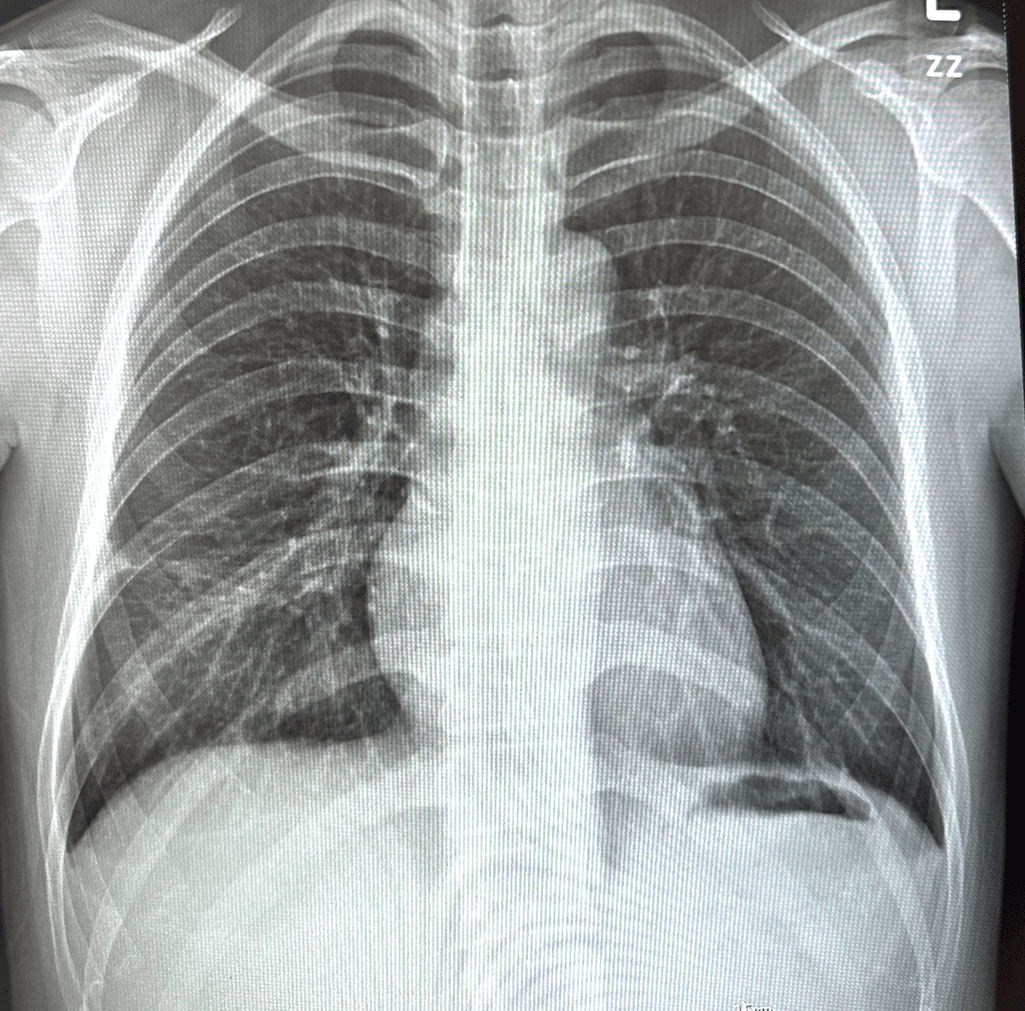

한국에서 9월 말 진료이기도 하고 미국 병원비도 너무.. 비쌀거 같아서 엑스레이만 찍었습니다. (아래 사진 첨부)

엑스레이 결과지에서는 흉수나 응고가 없다, 그리고 결절 크기만 적혀있습니다.

x ray는 호흡곤란이 발생할 정도의 상태는 아닌것 같습니다. 산소포화도가 96% 이상 나온다면 산소가 많이 부족한 상태는 아닌거 같습니다.. 심리적이나 다른 문제로 답답한 양상일수도 있을거 같은데요,,

x ray 나쁘지 않아요

현재 엑스레이 사진을 보았을 때에도 폐나 흉강 쪽의 병변이 크게 의심되지는 않는 상태이고 산소포화도도 정상인 것으로 보아 일시적일 가능성이 있겠으나, 폐암 병변이 커져서 기관지를 누르거나 침범하는 경우에 간혹 호흡곤란 증세가 발생하기도 합니다.